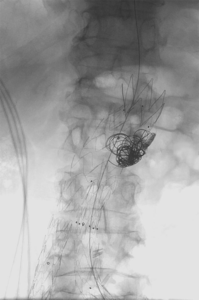

5. Thrombektomie – mechanische Entfernung von Blutgerinnseln

Wenn ein Gefäß durch Blutgerinnsel verschlossen ist, kann man den Verschluss mechanisch wiedereröffnen, indem man die Ablagerungen über spezielle Katheter absaugt. Dazu stehen uns Kathetersysteme, die mit Vakuum arbeiten bzw. zusätzlich die Gerinnsel vor dem Absaugen mit Hilfe von Wasserstrahlen oder Rotation der Katheterspitze zerkleinern, zur Verfügung.